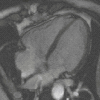

| Gradient echo (GRE) | Steady-state free precession | SSFP | Maintenance of a steady, residual transverse magnetisation over successive cycles.[59] | Creation of cardiac MRI videos (pictured).[59] |

|